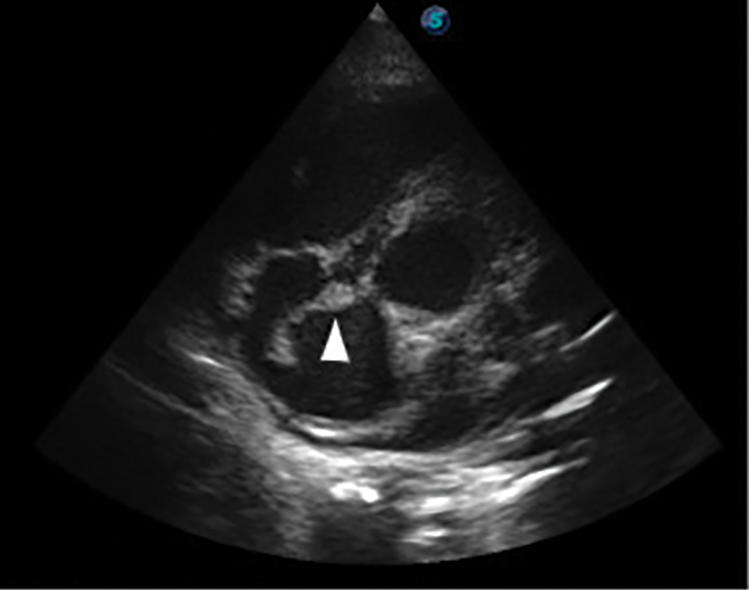

Further review and meticulous physical examination and investigations revealed confused and restless patient, febrile (T = 40°C), pale, acyanosed, RR: 38 breaths/min, SPO2 90%, pulse rate 122/min, blood pressure of 120/40 mmHg, Jugular venous pressure not raised, displaced apex and hyperdynamic, heart sound: S1, S2 and S3 gallop, PSM grade 3/6 loudest at 4th left intercostals space lateral to sternal border, tricuspid PSM grade 1/6 epigastrium, aortic diastolic murmur grade 2/4, bi-basal fine crackles. a provisional diagnosis of congenital heart disease (VSD) with aortic incompetence complicated by infective endocarditis, sepsis, AKI and acute left ventricular HF was entertained with differential diagnosis of Rheumatic heart disease (RHD) with complications. He was started on oxygen therapy and switched from generic ceftriaxone to the branded ceftriaxone (Rocephin). Metronidazole was stopped and gentamicin added adjusted for renal function, he also received furosemide along with conservative renal therapy and close monitoring. Additional relevant investigations were requested which include (1) Laboratory test as indicated in (Table 1b) (2) Electrocardiogram (ECG) which showed sinus tachycardia with heart rate of 115 beat per min (Fig. 1). (3) Chest X-ray (CXR): Showed cardiomegaly of biventricular configuration with cardiothoracic ratio of 0.61, prominent pulmonary vasculature, upward blood diversion and blunted left costophrenic angle (Fig. 2). (4) Transthoracic echocardiography (TTE): revealed interventricular septal thickness of 9.4 mm and left ventricular posterior wall thickness of 13.5 mm. Moderately dilated left ventricle (LV) with internal diameter of 66.4 mm, mildly dilated left atrial with internal of diameter 44.1 mm, mildly dilated right ventricle with internal diameter of 43.9 mm, moderately dilated right atrium with internal diameter of 53.2 mm, Peri-membranous VSD measured 5.3 mm in size with color Doppler demonstrating left to right shunt (Fig. 3A,B). Aortic valve prolapse of the non-coronary cusp 4.5 mm from the plane and severe aortic regurgitation [Width of vena contracta of 7.4 mm and regurgitant jet width/LV out flow tract diameter ratio of 2.1 cm/2.6 cm of 0.80 (80%)] (Fig. 4A,B), large oscillating echogenic mass attached to tricuspid valve leaflet was noted (Fig. 5) and (Supplementary Materials Video S1). LV Ejection fraction (EF) was 64.7% on M-mode guided 2-D with fractional shortening of 36.3% and normal RV systolic function (TAPSE: 20.4 mm). LV end-diastolic volume index was 135.8 mL/m2 (Severely abnormal), while LV end-systolic volume index was 47.9 mL/m2 (Severely abnormal) and LV mass index (LVMI) was 209.3 g/m2 (Severely abnormal). Other heart valves appeared normal in motion and morphology. Moderate mitral regurgitation, severe tricuspid regurgitation and mild pulmonary regurgitation were noted. Pulmonary arterial systolic pressure at rest was 52.2 mmHg.

Figure 5: Transthoracic echocardiography (TTE) parasternal short axis view, arrow head showing large tricuspid valve vegetation